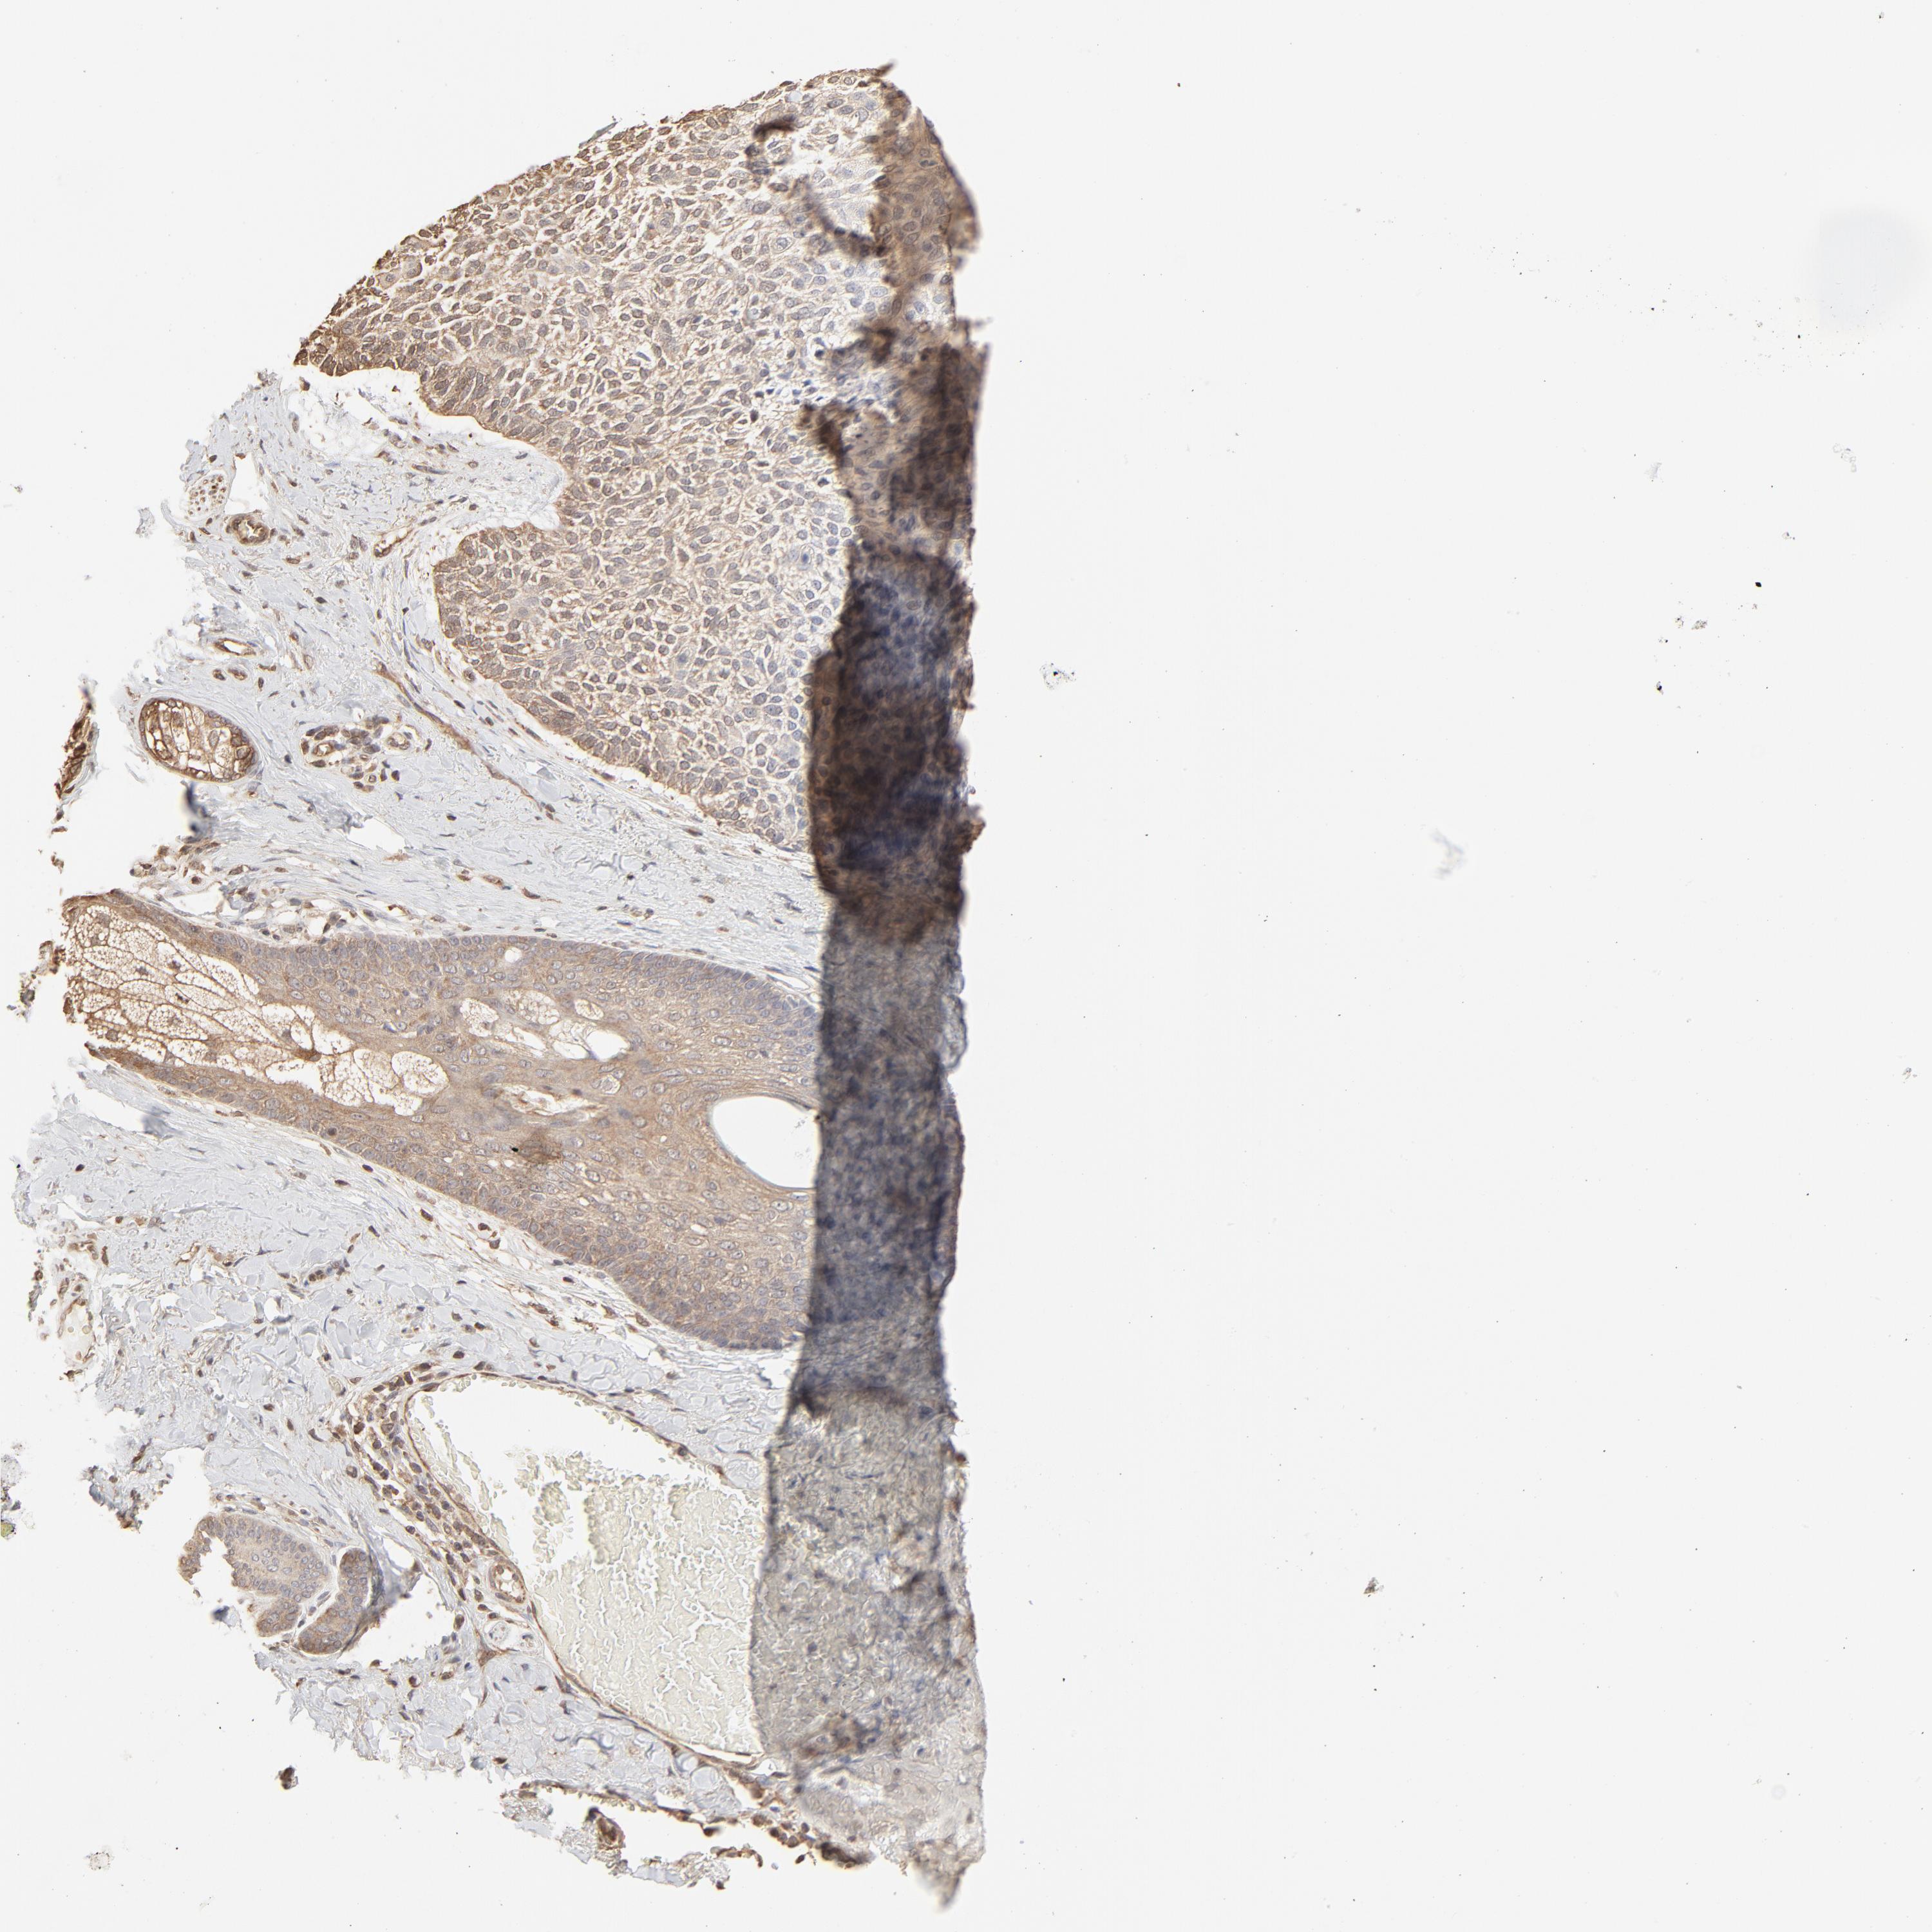

SKIN CANCER - Protein expressioni

A mouse-over function shows sample information and annotation data. Click on an image to view it in a full screen mode. Samples can be filtered based on level of antibody staining by selecting one or several of the following categories: high, medium, low and not detected. The assay and annotation is described here.

Antibody stainingi

Antibody staining in the annotated cell types in the current human tissue is reported as not detected, low, medium, or high, based on conventional immunohistochemistry profiling in selected tissues. This score is based on the combination of the staining intensity and fraction of stained cells.

Each image is clickable and will lead to virtual microscopy that enables deeper exploration of all samples and also displays staining intensity scores, fraction scores and subcellular localization as well as patient and tissue information for each sample.

Antibody HPA043236

Antibody CAB003848

Squamous cell carcinoma, NOS

Squamous cell carcinoma, metastatic, NOS